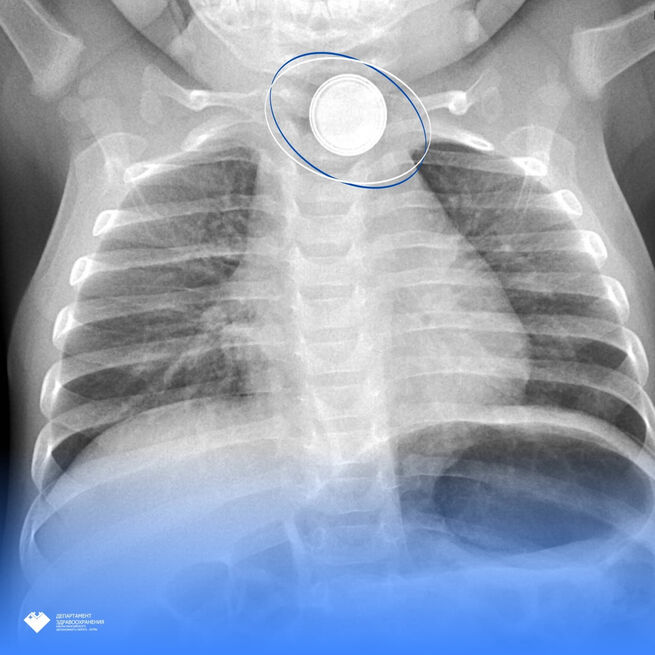

Как рассказали в пресс-службе Здравоохранения Югры, в Нефтеюганскую районную больницу на скорой привезли 11-месячного малыша. Родители заподозрили, что ребенок проглотил опасный предмет и решили вызвать врачей. Рентген подтвердил, что в теле младенца находился инородный предмет, который застрял в верхней части пищевода. Когда врачи об этом узнали, ребенка срочно эвакуировали в Сургут в Центр охраны материнства и детства.

– Там маленький пациент поступил в детское хирургическое отделение №3. Повторное эндоскопическое исследование выявило критическую ситуацию: аккумулятор диаметром 1,5 см вызвал тяжелый электрохимический ожог 3 степени. Было принято решение о срочной операции, – сообщили в пресс-службе.

Команда медиков провела успешную операцию, избавив малыша от опасного предмета в пищеводе. Через месяц врачи вновь обследовали маленького пациента и в этот раз не нашли никаких осложнений, его пищевод восстановился. Сейчас он дома, но за ним по-прежнему наблюдают, передает издание Ugra-news.ru.